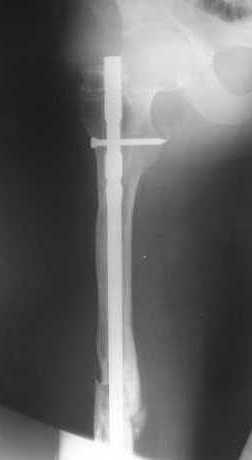

> Хмм..интересные мысль на счет использования большеберцового

> гвоздя...опять же, хочется наглядности:)

В приложении как раз видна эволюция использововшихся у нас большеберцовых гвоздей. Первый - дизайн как у UTN, второй - разнесены 45 градусные отверстия (зачем их вообще изначально так нелепо на одном уровне сделалм???), третий - убрано сиавшее лишним статическое отверстие, Herzog's bend перемещен более проксимально.